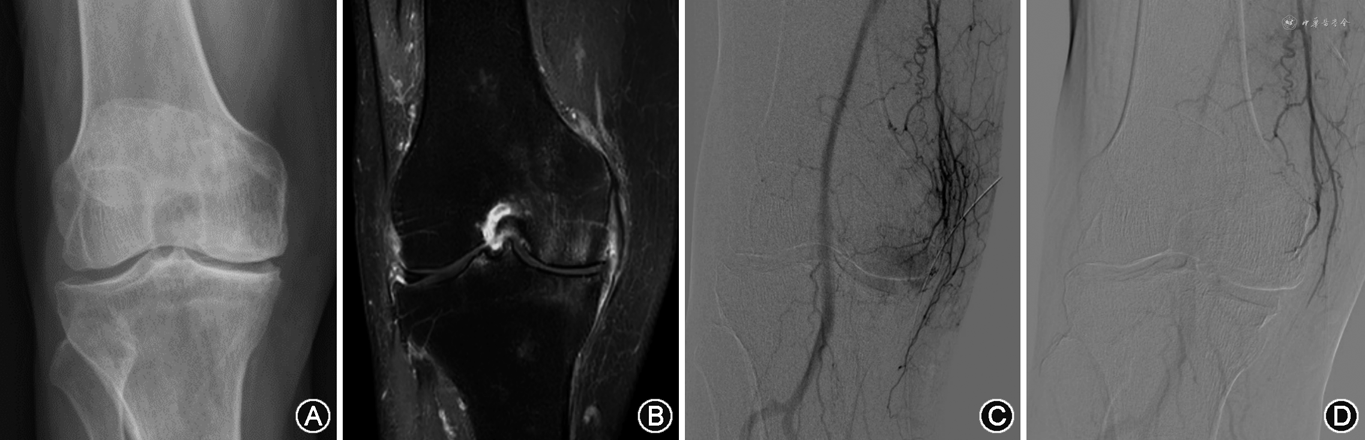

23侧患膝均超选并栓塞3~7支膝动脉分支,其中7例K-L分级4级患者栓塞4~7支膝动脉分支。23侧患膝完成6个月以上随访:GAE术后1个月临床改善率为95.6%(22/23),3个月临床改善率为86.9%(20/23),6个月临床改善率为91.3%(21/23),2例K-L分级4级患者归入临床失败。VAS评分、WOMAC疼痛评分及WOMAC总评分术后1、3、6个月分别降低63%、71%及59%,56%、62%及53%,59%、65%及57%。所有患者术后1、3、6个月VAS评分、WOMAC疼痛评分、WOMAC总评分与术前相比,差异均有统计学意义(均P<0.01)(表2)。典型病例影像资料见图1。

双侧腹股沟区消毒铺无菌巾,2%利多卡因局部麻醉后采用Seldinger法穿刺股动脉,以对侧逆行方式建立动脉入路,置入5 F血管鞘,送入5 F造影导管。分别行股浅动脉及腘动脉数字减影血管造影(digital subtraction angiography,DSA),以观察膝关节周动脉血管情况。使用同轴2 F微导管进行选择性膝动脉造影,主要包括髌上动脉、膝降动脉、膝上和膝下内外侧动脉、膝中动脉和胫前返动脉,观察各分支动脉是否存在新生血管及异常染色,尤其关注患侧膝关节压痛区域[9]。发现异常血管增生或异常染色后进行栓塞,使用聚乙烯醇颗粒(150~350 μm)20~100 mg作为栓塞剂,术中用20 ml碘造影剂稀释,透视下缓慢进行自由流动栓塞,以初始血管造影异常染色明显减少或消失为栓塞终点。技术成功定义为选择性栓塞至少1条异常染色膝关节动脉[7]。栓塞结束后手动压迫止血。双侧膝关节病变患者采用分次分侧治疗。